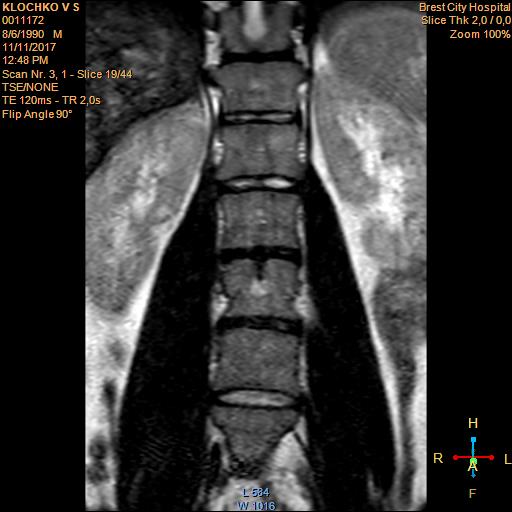

Тренировки с межпозвоночной грыжей.